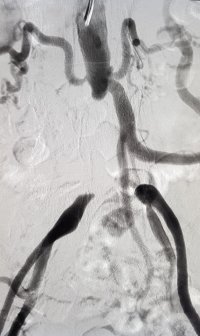

CT Angiography

CT Angiography (CT guided non-invasive angiography) is a highly confirmatory test and helps in exact treatment and management plan. By this test, we can evaluate the exact site, extent, and type of blockages, as well as the size of blood vessels (we can decide whether blockages can be treated by angioplasty or will require a peripheral bypass). This provides a road map which helps us keep planning further treatment.